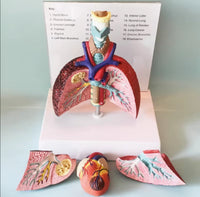

Modelo cardiopulmonar sistema respiratorio laringe

El modelo cardiopulmonar muestra Laringe humana, modelo pulmón cardiopulmonar, corazón, laringe, tráquea, nodos linfáticos, caja torácica médica